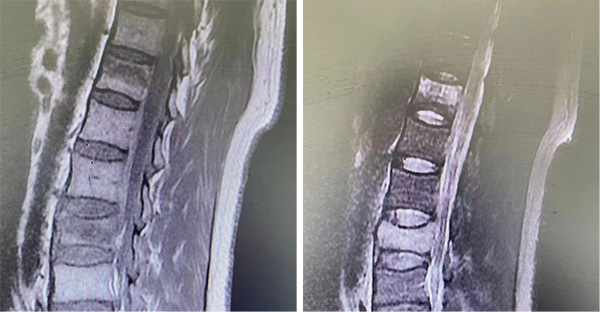

图|术前影像资料-胸12、腰3椎体骨折

患者为54岁的维吾尔族男性,因“高处坠落伤致腰部及双下肢活动受限3小时”入院。经诊断“腰3椎体爆裂骨折、胸12椎体压缩性骨折”。何鹏宇医师经查体、综合评估判断患者手术指征明确,与患者及家属充分沟通后,带领科室同事一起为其制定手术方案。

术后影像资料显示,内固定及骨水泥位置满意,手术的成功开展实现了新疆洛浦县人民医院创伤骨科腰椎骨折椎弓根系统内固定及微创手术零的突破,填补了脊柱骨折这类疾病手术治疗的空白。